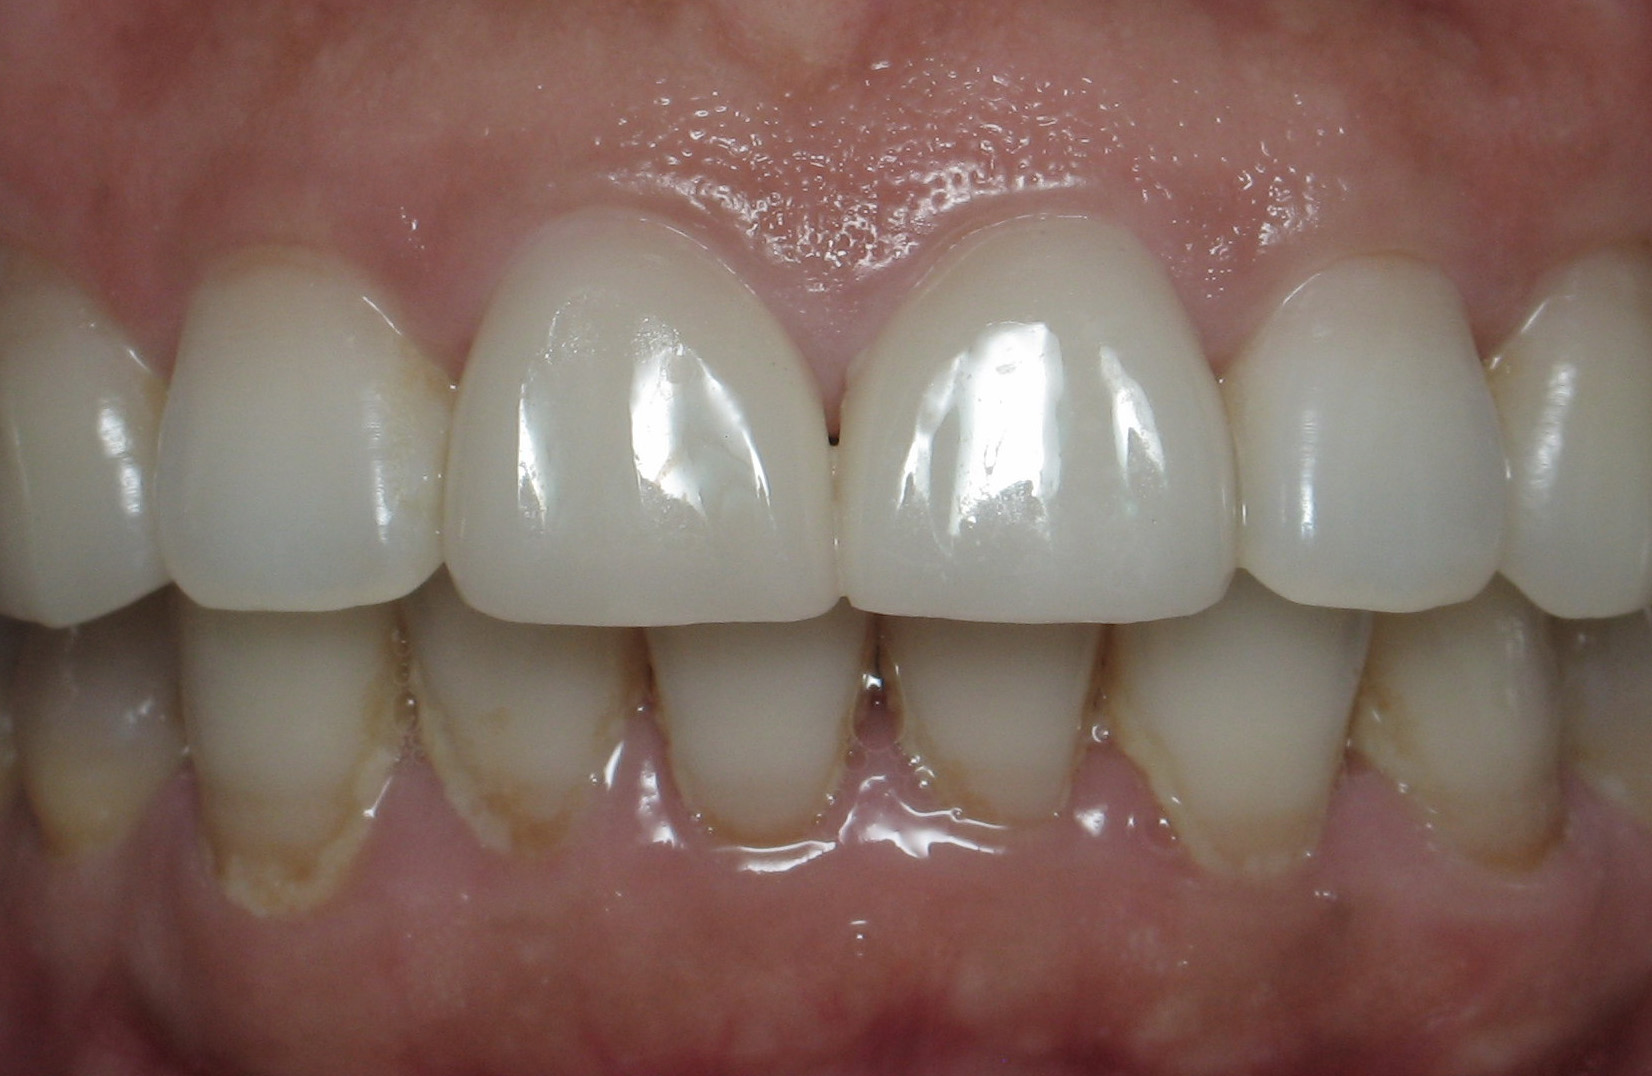

Smile Gallery

Orthodontic Treatment X-ray - Before

After Series of Teeth Extractions, Upper Left Canine Unerupted.

Ready to Start Ortho Treatment

Orthodontic Treatment X-ray - After